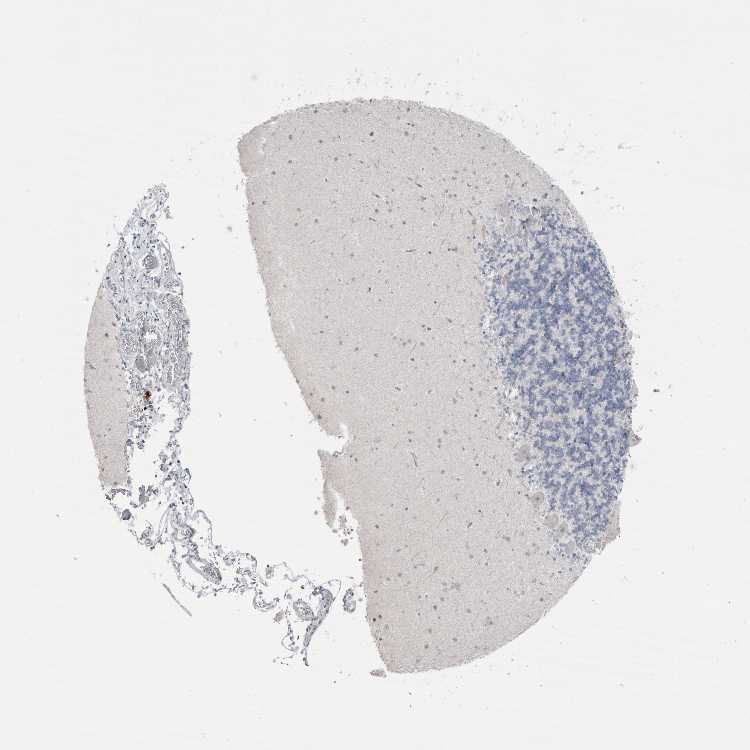

CEREBELLUM - Antibody stainingi

Antibody staining in the annotated cell types in the current human tissue is reported as not detected, low, medium, or high, based on conventional immunohistochemistry profiling in selected tissues. This score is based on the combination of the staining intensity and fraction of stained cells.

Each image is clickable and will lead to virtual microscopy that enables deeper exploration of all samples and also displays staining intensity scores, fraction scores and subcellular localization as well as patient and tissue information for each sample.

Antibody HPA023614Antibody HPA023616Antibody HPA026556Antibody CAB025143

Purkinje cells Not detectedNot detectedNot detectedNot detected

Cells in granular layer Not detectedNot detectedNot detectedNot detected

Cells in molecular layer Not detectedNot detectedNot detectedNot detected